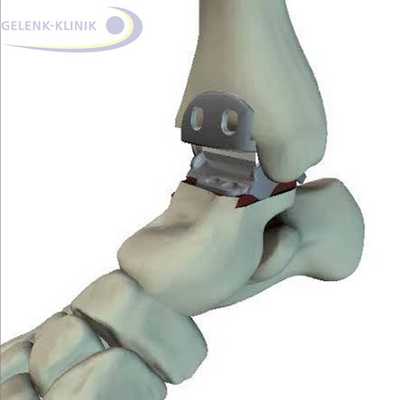

В Геленк Клинике применяются различные пластические методики. При пластике внешней связки её пытаются восстановить с помощью импланта из собственной ткани. Для этого используются остаточные элементы, части надкостницы латеральной лодыжки и ткани суставной капсулы. Если этих тканей недостаточно, то используются имплантаты сухожилий. Для этого изымаются части, проходящие в непосредственной близости от внешней связки, и затем пересаживаются в сустав.

Хирурги Геленк Клиники проводят восстановление голеностопного сустава при хронической нестабильности по методу Brostöm. При этом оставшиеся элементы служат для анатомического восстановления. Во время операции они собираются, а затем растягиваются, чтобы достичь первоначальной длины связок. Для обеспечения стабильности, части разгибательных сухожилий перемещаются в сторону латеральной лодыжки и сшиваются.